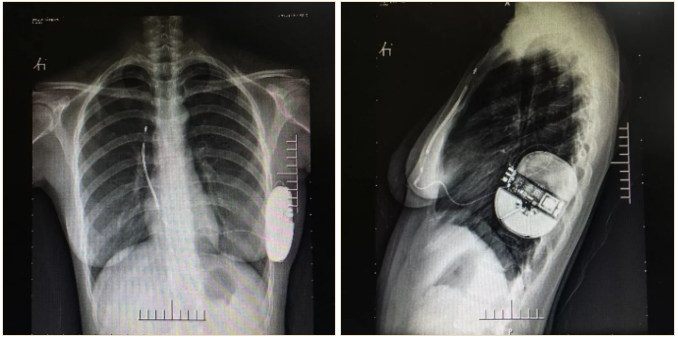

术后X线影像

术后测试优化,参数位于正常范围内。手术圆满成功,耗时约1小时。